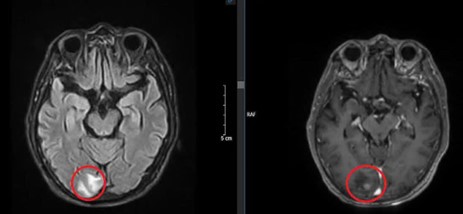

Hình ảnh chụp cắt lớp vi tính lồng ngực sau 3 chu kỳ điều trị hóa chất:

Trước điều trị

Sau điều trị

Hình 3: Hình ảnh chụp cắt lớp vi tính lồng ngực trước và sau điều trị

Nhận xét: Trước điều trị hóa chất thùy dưới phổi trái có khối tỷ trọng ngấm thuốc, thượng đòn phải và trung thất có vài hạch, nhóm 2, 4 bờ rõ, ngấm thuốc sau tiêm, các hạch dọc động mạch chủ bụng ngấm thuốc, tuyến thượng thận trái dày thân tuyến, tuy nhiên sau điều trị hóa chất 3 chu kỳ, không thấy hình ảnh khối tỷ trọng ở phổi, các hạch ở trung thất, thượng đòn, dọc động mạch chủ bụng cũng như hình ảnh dày thận tuyến thượng thận.